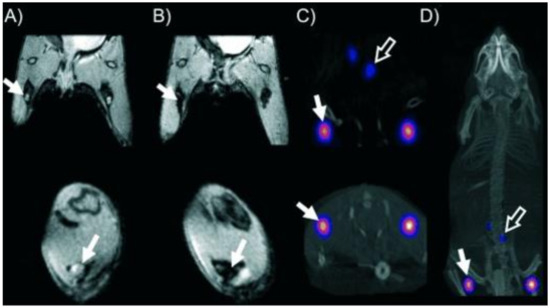

7.7. Application of Dithiocarbamate in Medical Imaging

- Berry, D.J.; Torres Martin de Rosales, R.; Charoenphun, P.; Blower, P.J. Dithiocarbamate complexes as radiopharmaceuticals for medical imaging. Mini Rev. Med. Chem. 2012, 12, 1174–1183. [Google Scholar] [CrossRef]

- Mathur, A.; Mallia, M.B.; Subramanian, S.; Banerjee, S.; Kothari, K.; Dhotare, B.; Sarma, H.D.; Venkatesh, M. 99mTcN complexes of tert-butyl dithiocarbamate and methoxyisobutyl dithiocarbamate as myocardial and brain imaging agents. Nucl. Med. Commun. 2005, 26, 1013–1019. [Google Scholar] [CrossRef]

- Torres Martin de Rosales, R.; Tavaré, R.; Paul, R.L.; Jauregui-Osoro, M.; Protti, A.; Glaria, A.; Varma, G.; Szanda, I.; Blower, P.J. Synthesis of 64CuII–bis (dithiocarbamatebisphosphonate) and its conjugation with superparamagnetic iron oxide nanoparticles: In vivo evaluation as dual-modality PET–MRI agent. Angew. Chem. 2011, 123, 5623–5627. [Google Scholar] [CrossRef]

- Zhang, J.; Guo, H.; Zhang, S.; Lin, Y.; Wang, X. Synthesis and biodistribution of a novel 99mTcN complex of ciprofloxacin dithiocarbamate as a potential agent for infection imaging. Bioorganic Med. Chem. Lett. 2008, 18, 5168–5170. [Google Scholar] [CrossRef]

- Lin, X.; Jin, Z.; Ren, J.; Pang, Y.; Zhang, W.; Huo, J.; Wang, X.; Zhang, J.; Zhang, Y. Synthesis and Biodistribution of a New 99mTc-oxo Complex with Deoxyglucose Dithiocarbamate for Tumor Imaging. Chem. Biol. Drug Des. 2012, 79, 239–245. [Google Scholar] [CrossRef]